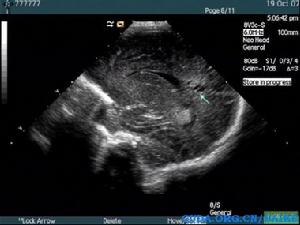

超聲診斷

腦白質軟化早期超聲可見腦室周邊白質回聲增強,邊界不清,沒有占位效應,如果沒有這方面的意識,此時容易漏診,因此在顱腦超聲檢查時,能夠顯示各個腦室的切面均需觀察其附近腦白質回聲是否均質,有無回聲增強,隨著時間推移,其內可見液性囊區,比較容易被超聲發現!新生兒缺血缺氧性腦病、顱腦損傷為常見病因。

一般這種患兒多在新生兒期檢出,有顱內感染、宮內感染或者產傷的病史,顱腦超聲檢查時需注意腦白質回聲是否均質,早期病變與周圍正常組織對比度不是很明顯,易漏診!